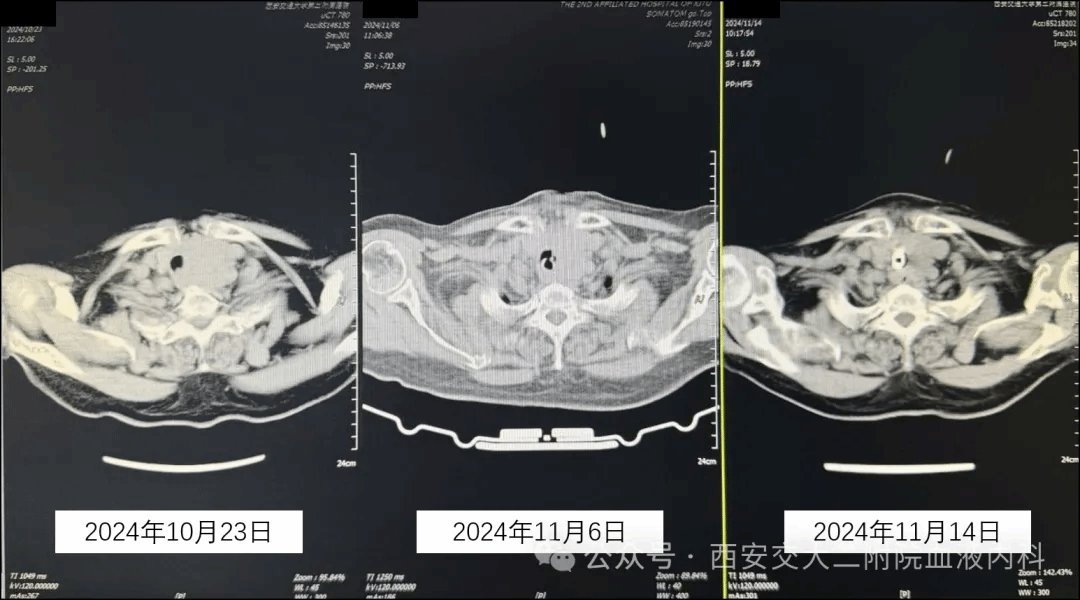

收住入院后患者憋气症状进行性加重,康全清教授、侯瑾教授及闫妍医生团队紧急组织病历讨论,为缓解症状急诊行暂时性气管切开并穿刺组织送病理会诊,结果出乎大家意料并非甲状腺肿瘤,而是较为罕见的经典型霍奇金淋巴瘤。病理结果回报后侯瑾教授立即与血液科曹星梅教授、古流芳教授取得联系,组织MDT讨论,考虑霍奇金淋巴瘤对化疗敏感,手术并非常规治疗选择,屈奶奶很快便转入了血液内科二病区继续治疗。曹星梅教授、古流芳教授及张亦琳医师充分评估患者病情,超高龄老年患者脏器储备功能不足、化疗耐受差、易出现严重骨髓抑制、合并严重感染等问题,但面对这个“卡脖子”的大家伙,一味减低剂量可能很难缓解屈奶奶的症状,最终讨论决定减低化疗剂量的同时加用ADC药物平衡疗效与副作用,同时在医护、临床营养科等相关科室的共同努力下,屈奶奶的憋气症状很快得到改善,目前已能正常吃饭、喝水了,夜间休息也有明显改善,CT检查提示肿物明显回缩,本周期治疗结束就可以回家休息一段时间了。